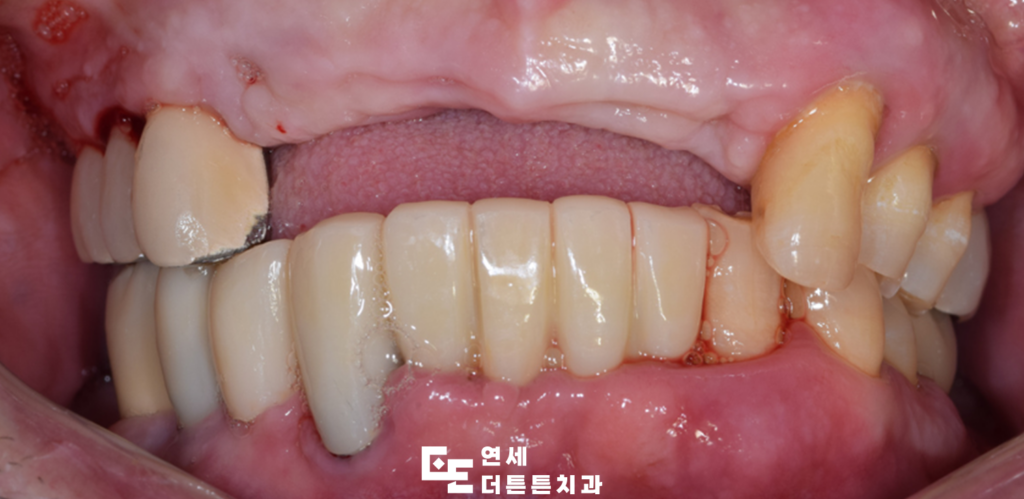

먼저 기존의 브릿지를 제거하고

자연치들을 발치하였습니다.

최종 보철물까지 완성한 모습입니다.

심미성과 가장 밀접한 관련이 있는 것은

최종 보철물의 재료로 과거에는 메탈 계열

혹은 세라믹 재료가 주로 사용되었으나

최근에는 심미성과 강도를 모두 갖춘

지르코니아 크라운 수요가 높아지고 있으며

높은 강도와 우수한 내구성을 갖추어

자연치에 가까운 색조 표현이 가능하고

알레르기 유발 가능성이 낮아

심미적 만족도가 높다고 평가됩니다.